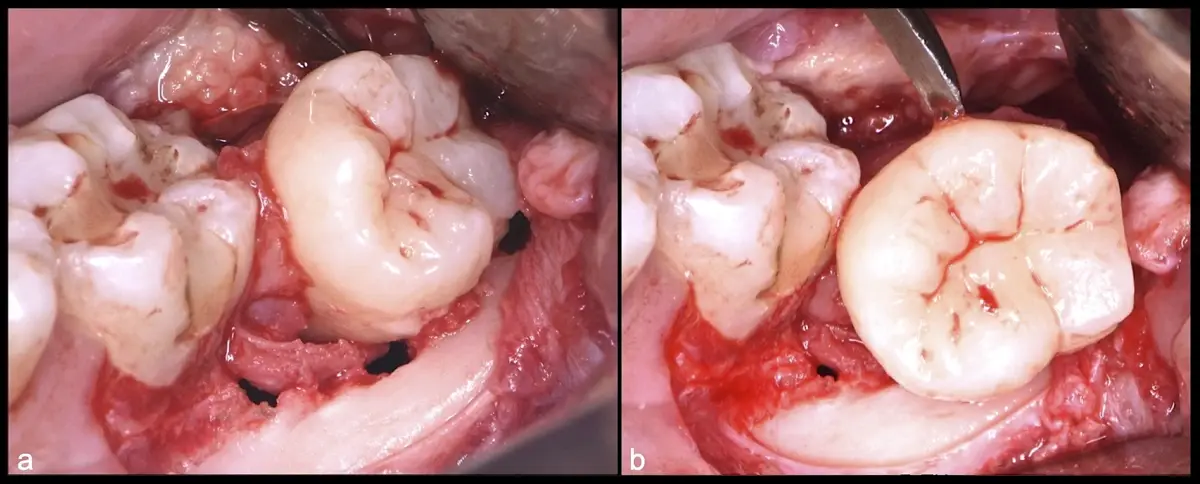

El procedimiento se inicia colocando anestesia troncular para bloqueo del nervio dentario inferior y sus ramas. Luego, se establecerá el diseño de acceso según la disposición de la molar a extraer. Para fines didácticos, se explicará cómo se realizaría la extracción de la molar de la Figura 1: se realiza una incisión horizontal a nivel de la zona retromolar hasta llegar a distal de la segunda molar, continuándose con una incisión intrasurcular hasta mesial de la segunda molar, finalizando con una incisión vertical a espesor total hasta llegar a la línea mucogingival (Figura 2).